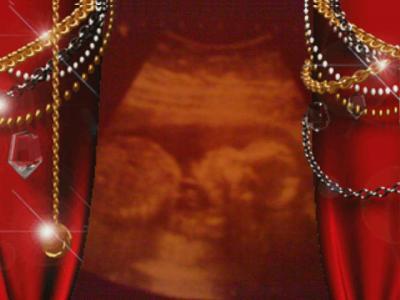

Aktuelles Ultraschallbild von unserem Liebling

Hier mal ein aktuelles US-Bild von unserem Schatz bei 22 + 3 VLG. Annabelle, Oli und Zwergi